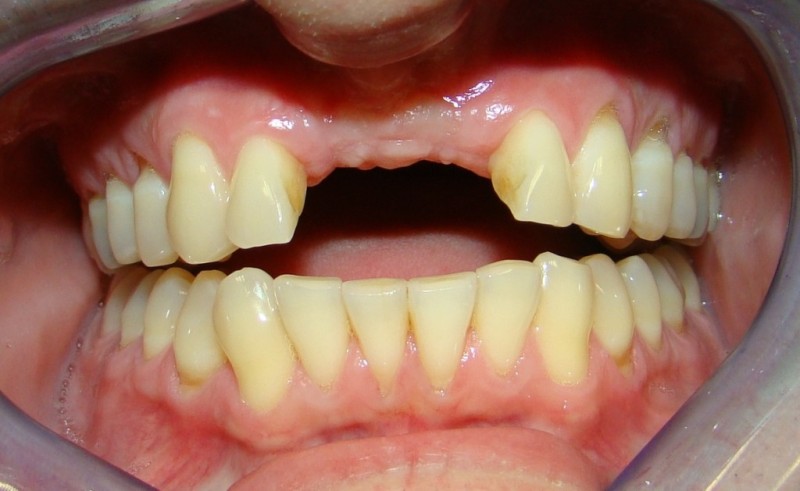

A Case with a Fractured Central Incisor